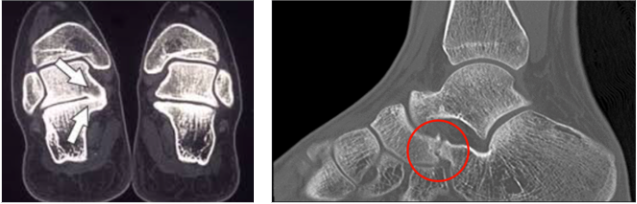

Pé plano rígido: as duas principais causas são: Coalizão Tarsal (distúrbio de formação/congênito – fusão de alguns ossos do pé) e Navicular Acessório (distúrbio de formação/congênito – ossículo extra/acessório). Essas alterações causam o aplainamento na formação do pé.

O diagnóstico de pé plano pode ser facilmente realizado pelo exame clínico do ortopedista especialista em pé e tornozelo. Os exames de imagem são úteis para diferenciar o tipo de pé (flexível ou rígido): a radiografia para avaliar a presença do ossículo extra/acessório ou a fusão óssea e a tomografia computadorizada para confirmar essa fusão óssea congênita.